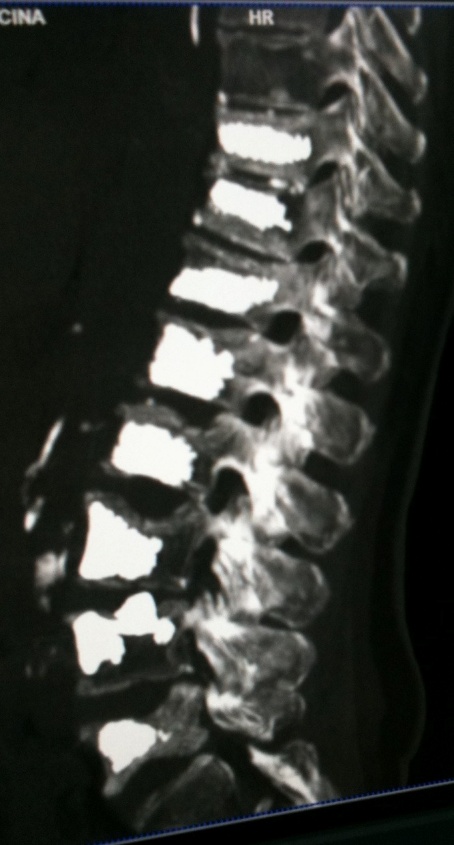

Vertebroplasty is a minimally invasive, image-guided procedure used to stabilize weakened vertebrae and provide rapid pain relief. It consists of injecting medical-grade bone cement (PMMA) into the vertebral body, restoring mechanical strength and reducing micromovements responsible for pain.

The procedure is performed under conscious sedation (local anesthesia with intravenous analgesia and mild sedation) or, in selected cases, general anesthesia.-

Percutaneous access through the pedicle under CT or fluoroscopic guidance

Precise needle positioning within the vertebral body

- Controlled injection of bone cement with real-time monitoring